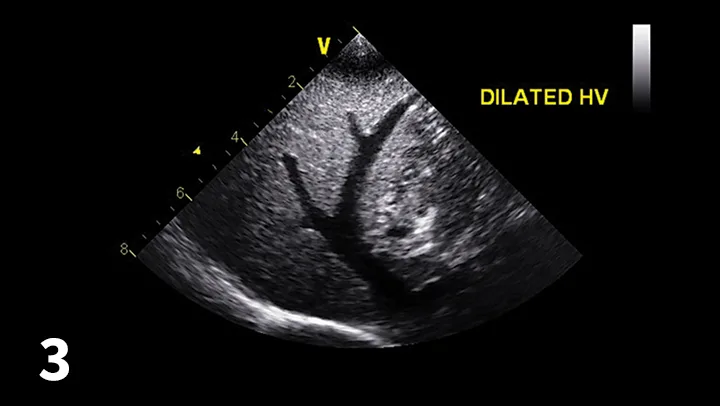

Lateral and VD thoracic radiographs of a dog with PHTN, showing mild right-sided enlargement of the heart and enlarged pulmonary arteries (arrows).

Thoracic radiographs are useful for evaluation but may underestimate the severity of the PHTN.

However, it may be possible to appreciate right-sided enlargement (reverse D) or pulmonary arterial enlargement (Figure 2).